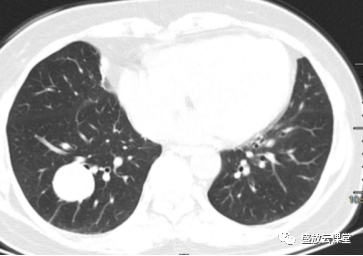

增强CT影像表现

右肺下叶基底段类圆形高密度影,大小约3.0cm×2.9cm

边缘规整,其内见点状钙化,增强扫描明显均匀强化

部位:右肺下叶、基底段

形状:类圆形

边界:边界清晰

密度:密度较均匀,其内见点状钙化

强化方式:均匀强化

影像学特点(CT):右肺下叶基底段类圆形高密度影,边缘规整,密度较均匀,其内见点状钙化,增强扫描明显均匀强化